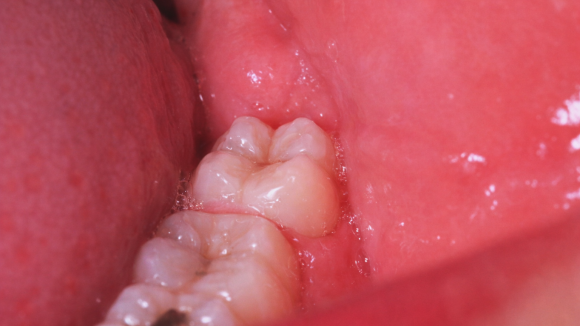

매복사랑니면

무조건 뽑아야 하나요?

사실 사랑니 발치 여부는

매복이냐 아니냐보다는

염증을 동반할 위험이 있느냐에 따라서

판단하게 되는데요.

맹출 경과를 관찰하면서

문제를 일으킬 가능성이 크다면

빠르게 발치를 진행합니다.

예를 들어, 매복 사랑니라고 해도

검진 결과에 큰 문제가 없다면

경과를 더 지켜볼 수도 있고

곧게 자란 사랑니여도

인접 치아에 영향을 주거나

염증을 발생시킬 것 같다면

발치를 진행하게 되겠죠.

사랑니 맹출 방향과 상관없이

잇몸이 반복적으로 붓거나

입을 벌릴 때 턱 뒤쪽에 뻐근한 통증이 발생하거나

어금니와 사랑니 사이에 음식물이 자주 끼는 경우,

그리고 원인 모를 구취가 지속되는 경우에는

사랑니로 인해 이미 염증이나 충치가

발생했을 수도 있으니

꼭 치과에서 정밀 검진을 받아 보시기 바랍니다.